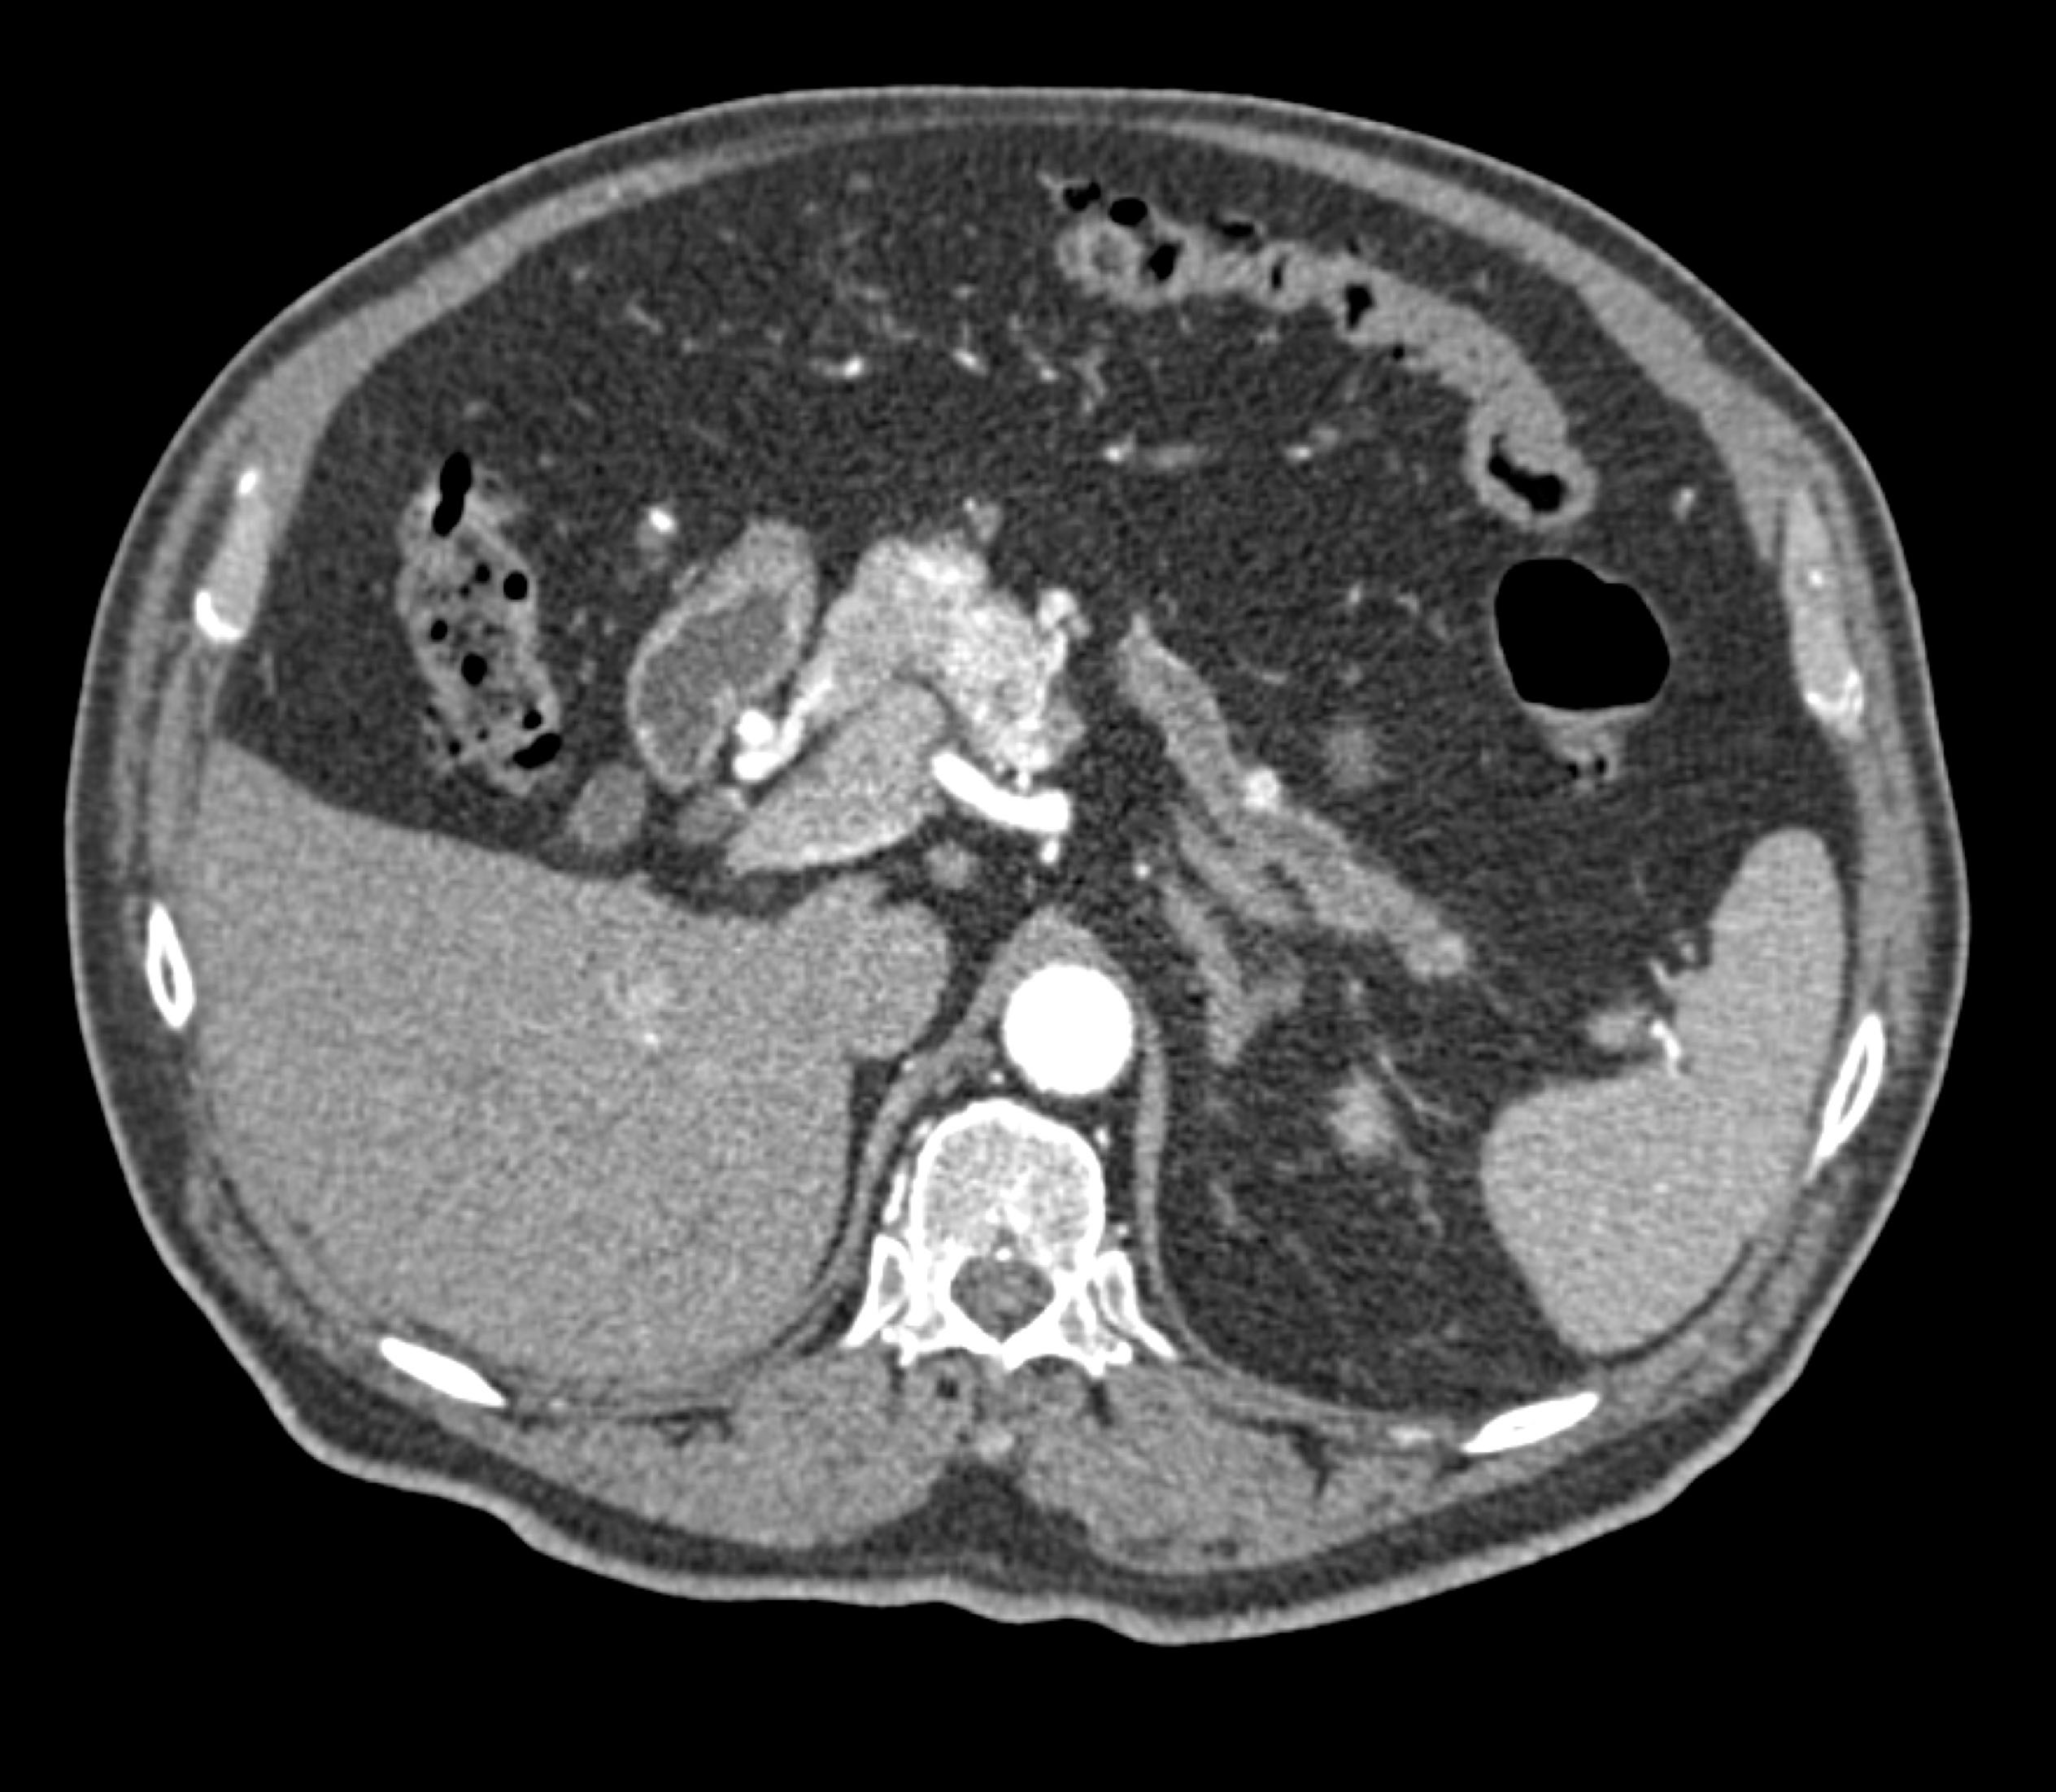

- Evaluate the CT images of each question carefully.

- Take time to make the call on the diagnosis for each individual question.